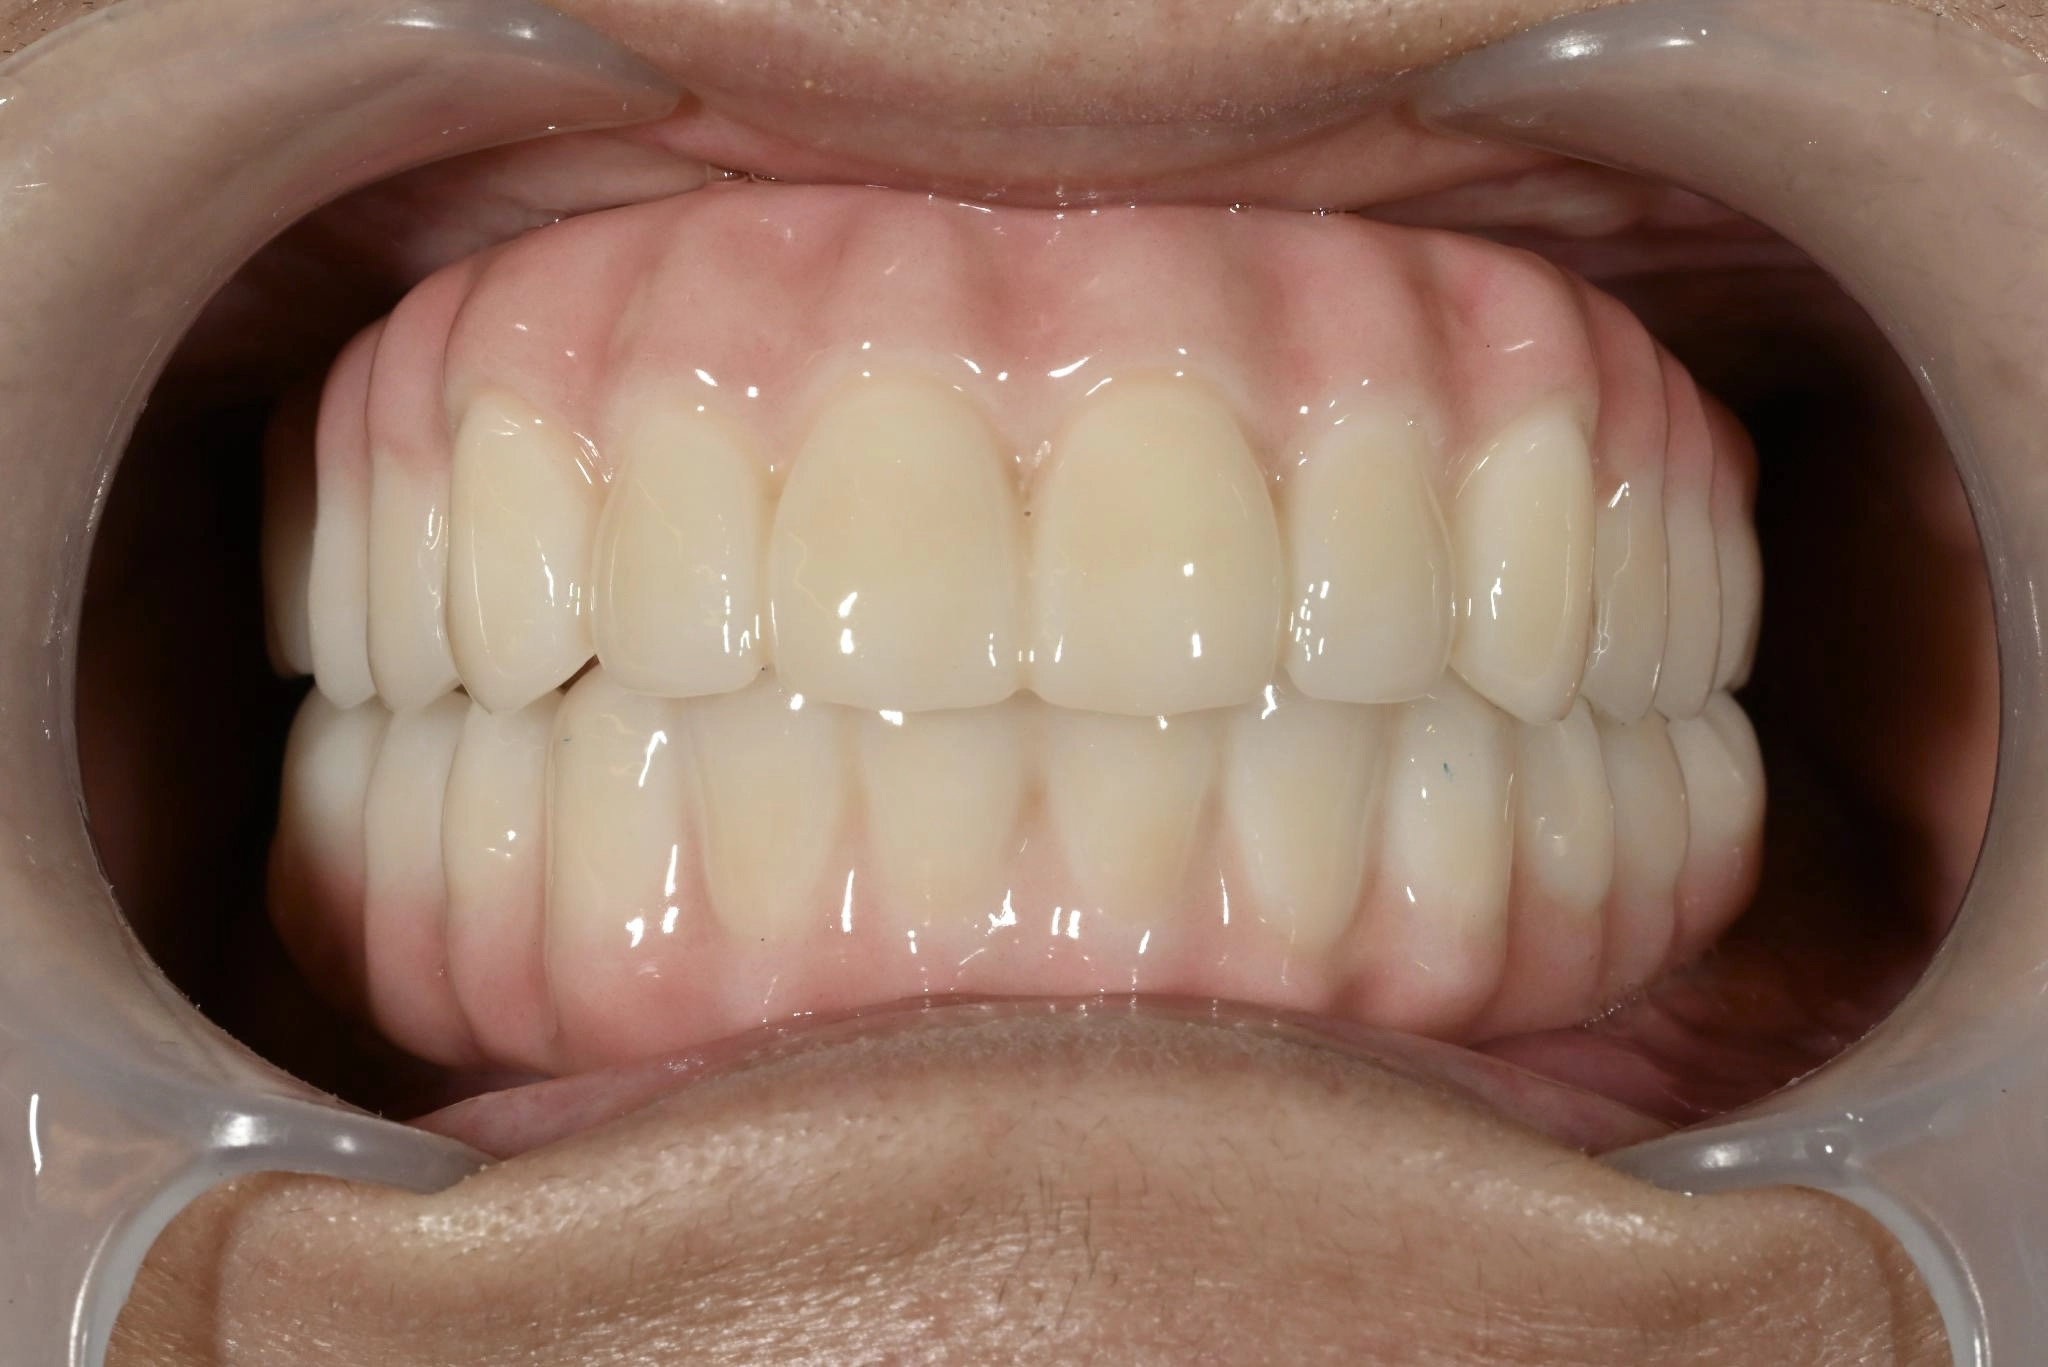

術後

内容 :上下顎オールオン4ザイゴマ2

費用 :5,552,800円

※モニター価格

期間 :半年

リスク:出血・腫れ・痺れ・痛み

手術前は恐さがありましたが、実際に始まるとあっという間に終わっていました。手術後、入った歯を見たときは綺麗で驚きました。今までの悩みがなくなり、手術をやって良かったと思います。自分と同じような歯の悩みを持つ人に勧めたいです。